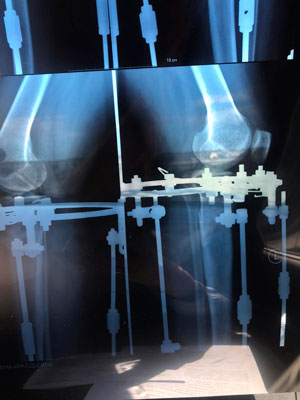

Исходник 32 года. Якутия

Дата операции - 05.02.2020г